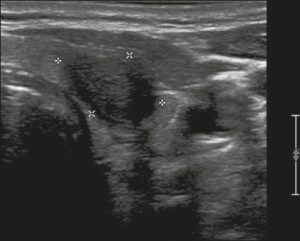

Ở đây, chúng tôi cung cấp các ví dụ minh họa việc áp dụng thực tế hệ thống ACR TI-RADS (Hình 18, 19, 20, 21). Các chú thích dưới hình mô tả chi tiết các mục đã được đánh giá và hiển thị điểm số trong ngoặc đơn.

Hình 21. Hình ảnh nhân giáp dạng đặc (2 điểm), giảm âm (2 điểm), cao hơn rộng (3 điểm), có đường bờ không xác định (0 điểm), và không có các ổ tăng âm hay bóng lưng (0 điểm). Do đó, tổng điểm là 7 điểm và mức độ nguy cơ được phân loại là TR5.